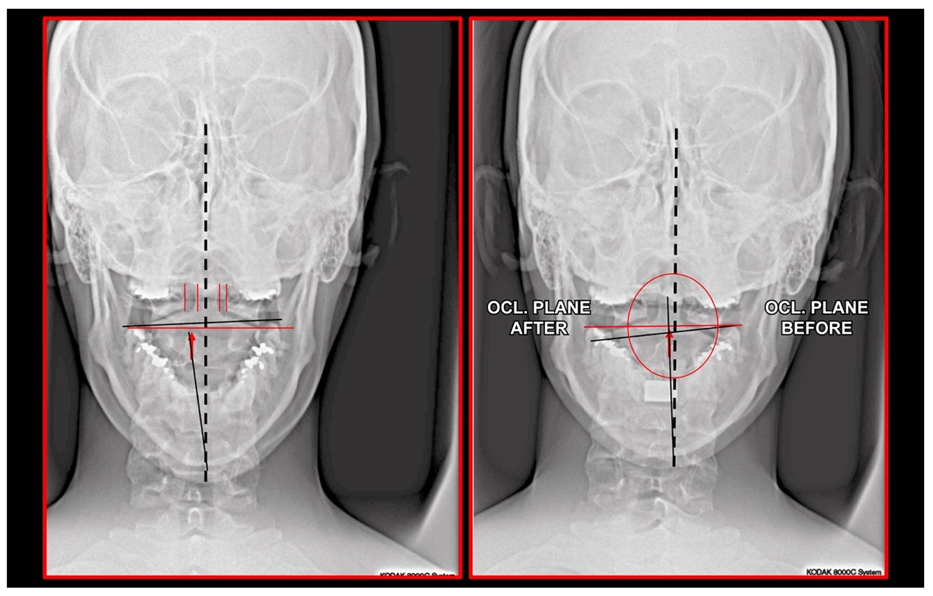

11.5. Axis and Atlas Derotation

11.7. Treatment of Occlusion